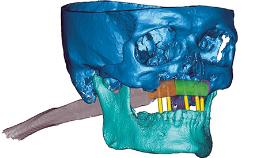

Rehabilitating an Edentulous Maxilla with a Fixed Dental Prosthesis Using a DSD-Guided Approach

A 60-year-old man was referred to the Center of Excellence for Prosthodontics and Implant Dentistry (CEPI) of the School of Dentistry of the University of São Paulo, Brazil for implant therapy. Anamnesis, clinical examination, and radiographs revealed esthetic and functional problems, the absence or structural compromise of various teeth (16–11, 21, 22, 24, 25, 37, 45, and 48), periodontal and endodontic problems (17 and 27), implant fracture (46), and occlusal disorders . The patient reported that he was undergoing treatment for cardiovascular diseases.